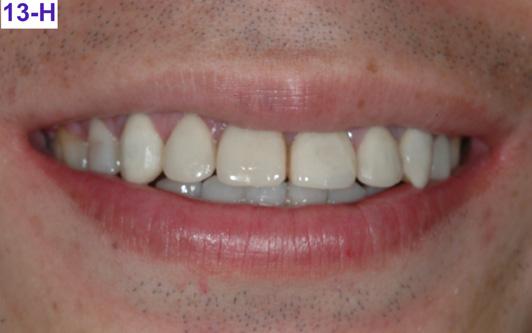

Please view the post-treatment images at the time of insertion of the retainers (Figure 13 – A, B, C. D, E, F, G, H, I, J, K, L).

Fig. 13H: Post-treatment, posed smile

Fig. 13K: Post-treatment, posed smile Text